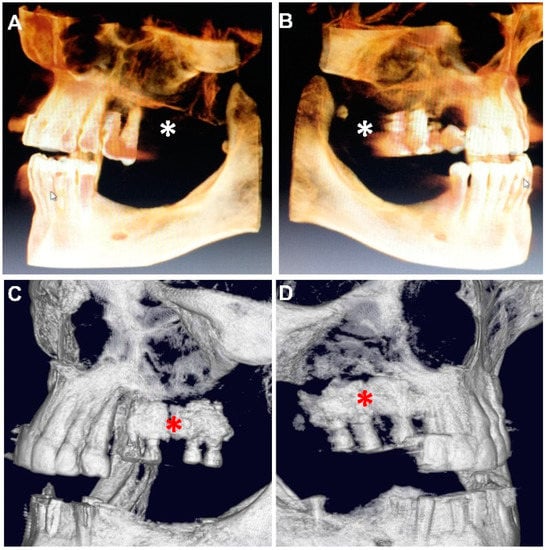

3. Results